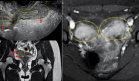

Los análisis de laboratorio no evidenciaron leucocitosis ni elevación de marcadores inflamatorios. Una tomografía computarizada (TC) abdominopélvica con contraste reveló líquido libre intraperitoneal sin presencia de neumoperitoneo, y se interpretó inicialmente como compatible con una posible torsión ovárica izquierda.

El equipo de ginecología procedió a una laparoscopia diagnóstica, en la cual se identificó un gran quiste ovárico sin torsión y una importante cantidad de líquido libre, sin evidencia de patología ginecológica que justificara los hallazgos. Ante esto, se solicitó la valoración del equipo de cirugía general, que realizó una segunda exploración laparoscópica, encontrando una perforación de 5 mm en la pared anterior del remanente gástrico.